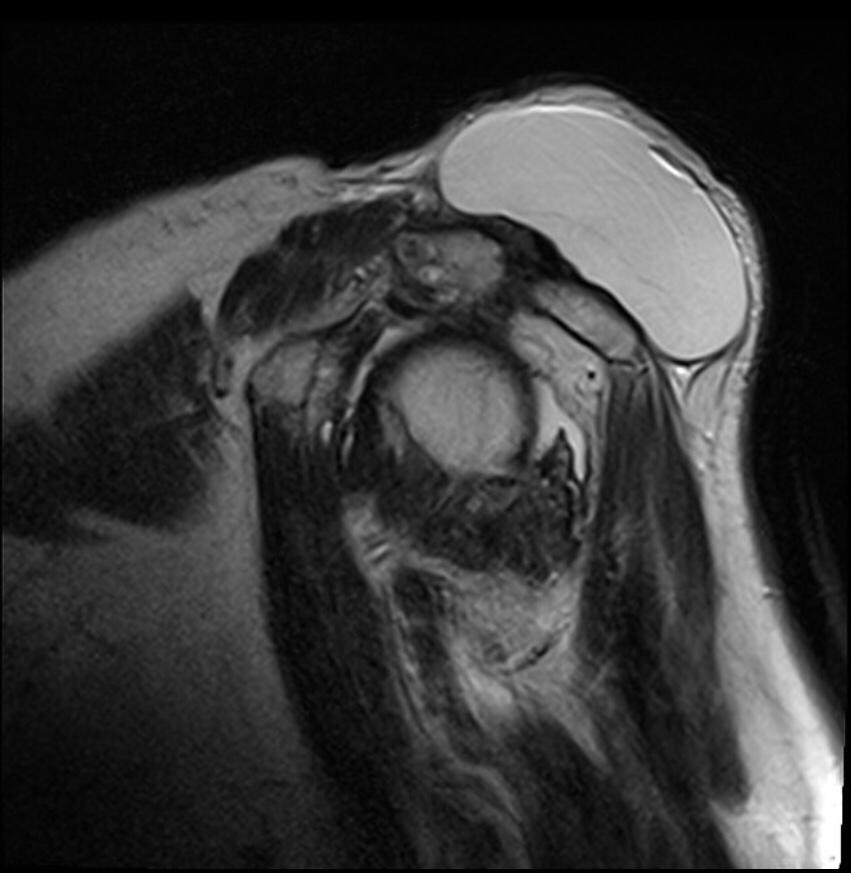

THE GEYSER SIGN IS A SUBCUTANEOUS PSEUDOTUMOR ABOVE THE ACROMIOCLAVICULAR JOINT

The geyser sign is a subcutaneous pseudotumor above the acromioclavicular joint, also known as AC joint cyst. The geyser sign is an infrequently encountered imaging sign that was originally described on conventional fluoroscopy-guided shoulder arthrography. The first case report of these cysts occuring in association with rotator cuff tears was made by Dr. Edward Craig in 1984, and again in 1986. The sign derives its name from its geyser-like appearance.

On physical examination, an AC joint cyst is a palpable fluid-filled mass. MRI scanning or a shoulder arthrogram should be obtained to evaluate the shoulder. Unenhanced MRI scans showing a large rotator cuff tear, a degenerated AC joint, and a large subcutaneous cyst adjacent to the AC joint is virtually patognomonic for the disease. Contrast administration on MR arthrogram will show the synovial fluid or intra-articular contrast extravasates from the glenohumeral joint into the subacromial bursa, into the AC joint, and then into an overlying cystic mass when a full-thickness rotator cuff tear is present, resembling a geyser spouting upwards.

Initial treatment is conservative and involves physical therapy along with aspiration. In patients with functional impairment or chronic shoulder pain who have failed conservative management, surgical treatment is recommended for both excision of the cyst and repair of the rotator cuff tear.